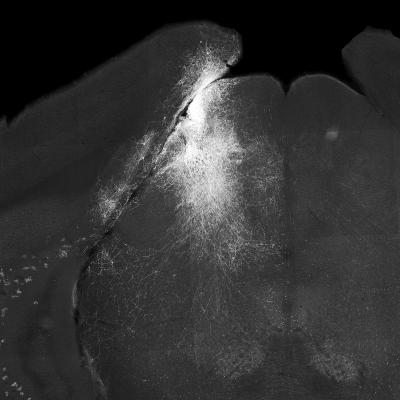

Grayscale slice of mouse brain with neurons highlighted

Slice of mouse brain showing neurons of the superior colliculus highlighted on one side. Image credit: Lupeng Wang, Ph.D. and Charles Gerfen, Ph.D.